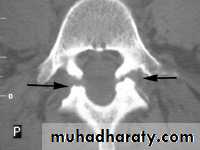

Two measurements are used: the mid-sagittal (anteroposterior) diameter and the inter-pedicular (transverse) diameter of the spinal canal. Normally, the diameters are 15 mm for the anteroposterior and 20 mm for the transverse. Anything less than 11 mm for the anteroposterior diameter and 16 mm for the transverse diameter is considered abnormal.

Imaging:X-rays will show features of disc degeneration or spondylolisthesis. Measurement of the spinal canal can be carried out on CT and MRI.